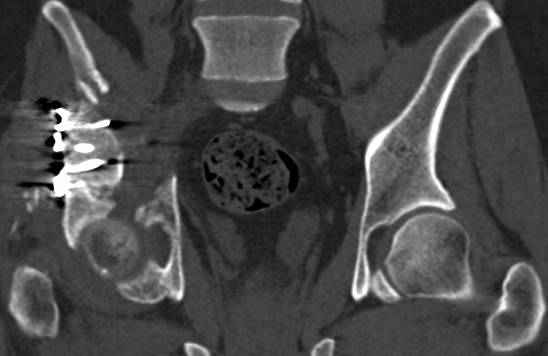

Интересно было бы посмотреть рентгенограммы до операции. У меня впечатление, что я не все вижу, что тут есть... Уважаемые Господа "тазисты" и "тазологи", к какому типу переломов вертлужной впадины по Летурнелю вы бы отнесли это случай?

Из переломов проходящих через крыло и/или заднюю стенку ни простой перелом "передней колонны" (явно имеется пером задней стенки, и не видно перелома седалищной или лонной), ни простой "поперечный", ни ассоциированный "Т-образный" (т.к есть перелом крыла и не видно перелома седалишной), ни ассоциированный "задняя колонна+задняя стенка", на ассоциированный "поперечный+задняя стенка", ни ассоциированный "передняя колонна+задняя гемисфера" (не видно перелома седалищной), ни ассоциированный "обе колонны" (не видно перелома лонной седалищной) не подходят под эту классификацию....

к таковым себя не причисляю, но...обычное дело для нашей страны - выкладывать 3D и не показывать стандартные проекции Judet. Дигност представляет те ракурсы, которые по-его мнению наиболее информативны, более того комп сам достраивает какие-то мелкие повреждения по 3D по своему усмотрению. По данной реконструкции можно предполагать высокий двухколонный перелом с оскольчатыми передней и задней колоннами, оскольчатую высокую переднюю колонну с задним полупоперечником или одно из перечисленных с вовлечение КПС. У меня впечатление за второй вариант, но нужно обследовать нормально - проекции, сканы.

высылаю дополнительно сканы.